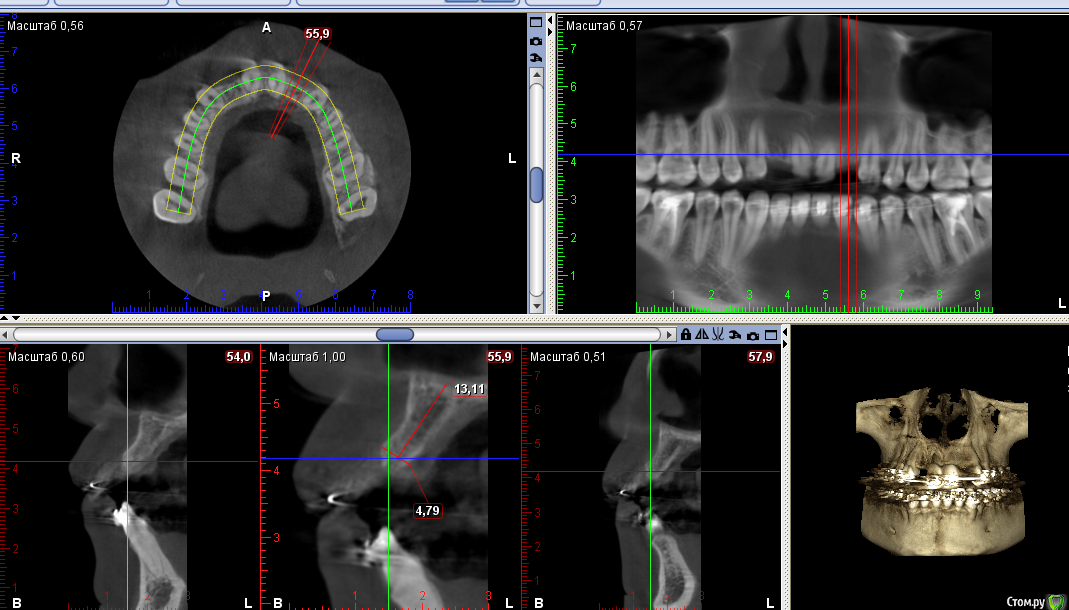

Тимур86 Опубликовано 22 сентября, 2016 Поделиться Опубликовано 22 сентября, 2016 Пациентка на ортодонтическом лечении.Нуждается в имплантации 12,22.В другой клинике предложили удалить 11 и 21 с костной пластикой,т.к. вестибулярно в области 11 отсутствует кость....Планируется установка Astra 3.0 в области 12 и 22 с использованием хирургического шабона,подсадкой СДТ и установкой ФДМ,через неделю временные коронки.Вопросы:1)зачем удалять 11 и 21? 2)нужна ли НКР? 3)можно ставить времяшки через неделю,учитывая подсадку СДТ? Ссылка на комментарий

колесников Опубликовано 22 сентября, 2016 Поделиться Опубликовано 22 сентября, 2016 Бред какой-то. Судя по снимку нет оснований ни для удаления,ни для нкр(с натяжкой 12),возможно визуально иначе. Поставил бы 3.5х9 ,сст и нагрузка. 2 Ссылка на комментарий